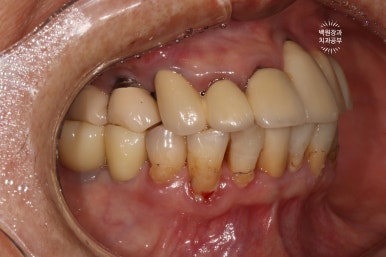

좌측은 위턱 사진, 오른쪽은 아래턱 구강내 사진입니다.

아주 어렵지 않게 두 치아가 부러져 있다는 것을 확인할 수 있죠.

오른쪽 측면 사진도 상당히 괜찮은 결과를 보여줍니다.

상황이 허락하여 모든 치아를 치료하진 않았지만, 가성비 최고의 결과를 얻은 것 같습니다.